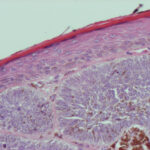

Superficial Basal Cell Carcinoma

Superficial BCC is characterized microscopically by buds of malignant cells extending into the dermis from the basal layer of the epidermis. The peripheral cell layer shows palisading. There may be epidermal atrophy, and dermal invasion is usually minimal. This histologic sub-type is encountered most often on the trunk and extremities but may also appear on the head and neck. There may be a chronic inflammatory infiltrate in the upper dermis.